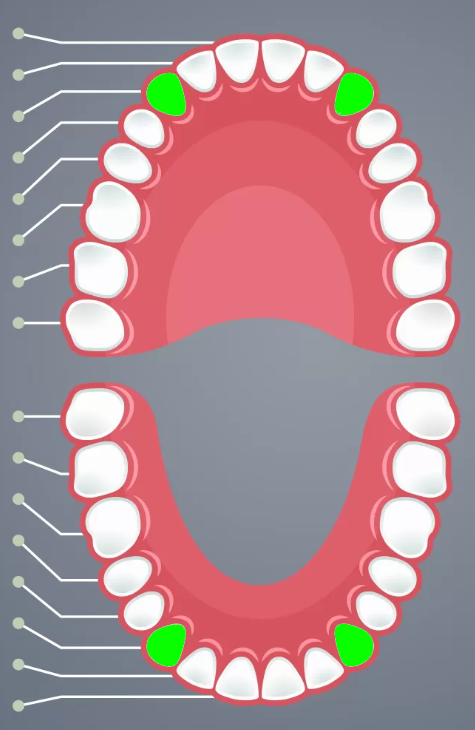

Incisors

Cuspids

Bicuspids

2nd molars

3rd molars